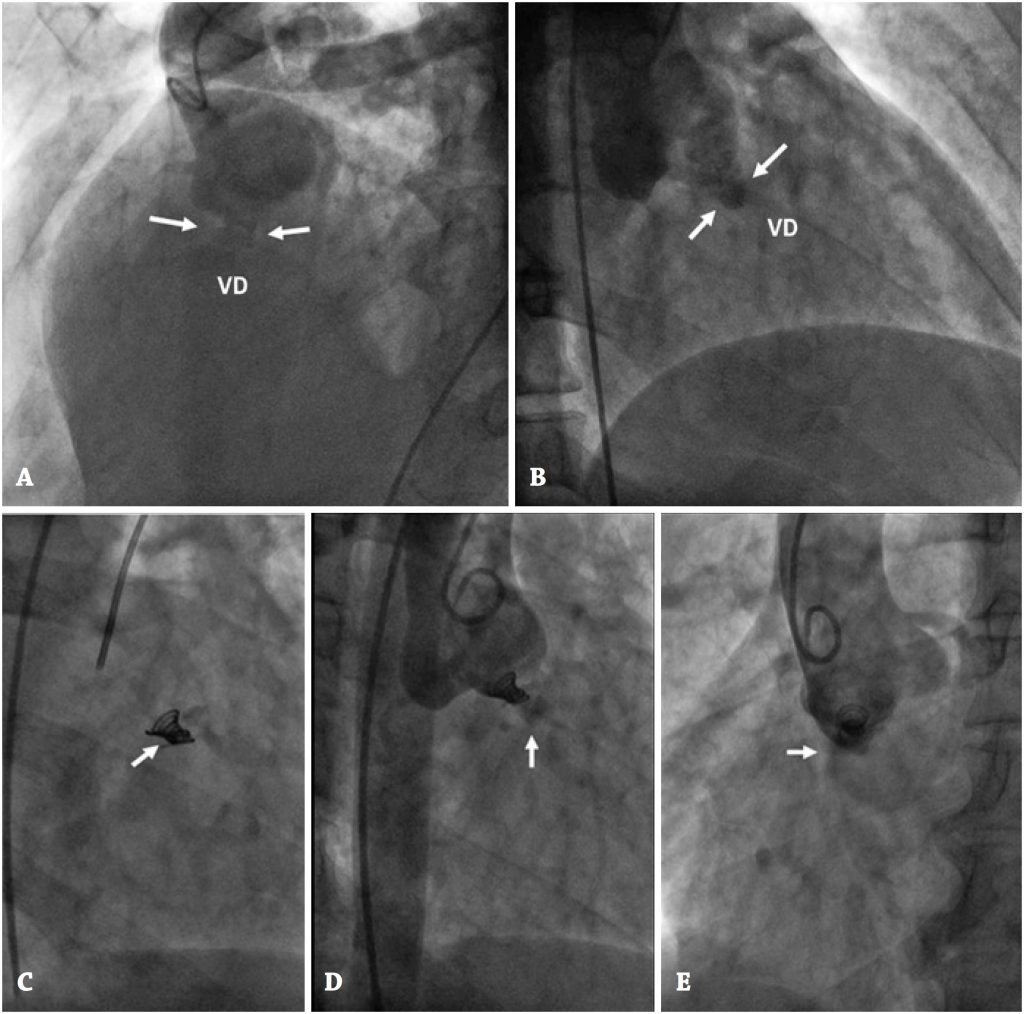

Os autores relatam dois casos de pacientes com aneurismas congênitos do seio de Valsalva, que romperam para dentro do ventrículo direito e foram ocluídos por via percutânea, com sucesso. Três dispositivos diferentes foram implantados por meio de duas abordagens diversas. O fechamento percutâneo justificou o implante de um dispositivo oclusor de canal arterial persistente, com abordagem transvenosa anterógrada, e de um coil mais um oclusor de comunicação interventricular, por via arterial retrógrada. Os procedimentos foram realizados sem complicações. A angiografia e a ecocardiografia, ao final das intervenções, demonstraram dispositivos bem posicionados. Os pacientes estavam assintomáticos, com os dispositivos em posição estável, sem shunt residual, após 6 meses de seguimento.